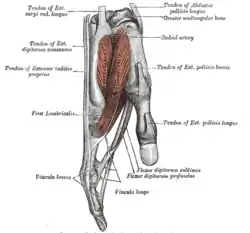

Ligaments of wrist. Anterior view Tendons of forefinger and vincula tendina.

Tendons of forefinger and vincula tendina.